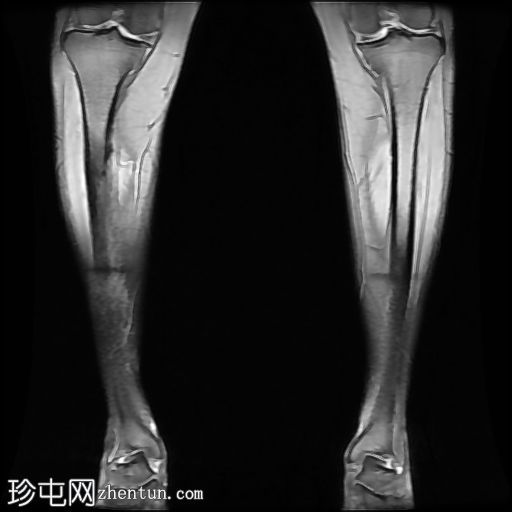

冠状位

T1加权像

内侧皮质可见一条低信号斜向皮质内线状影。

多发局灶性皮质内T2/STIR高信号病灶。皮质内可见一条线状信号异常区域。

邻近髓腔内广泛的骨髓水肿。

胫骨内侧缘骨膜水肿。